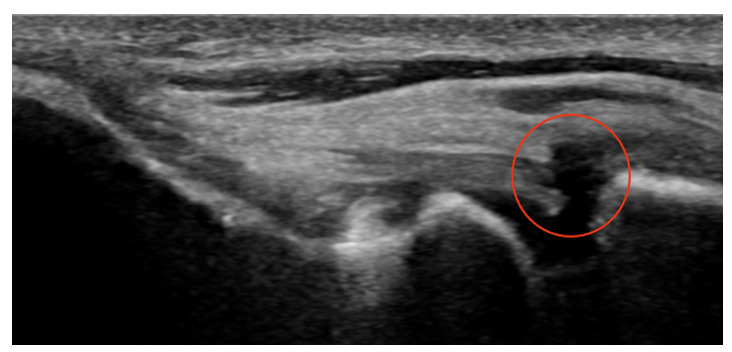

Diagnostic ultrasound imaging also serves as one of the diagnostic tools for evaluating the UCL for injuries.11 The anterior band of the UCL is identified originating at the medial epicondyle and inserting in the sublime tubercle. An intact UCL has homogenously hyperechoic collagen fibers tapering down towards the sublime tubercle (Figure 8). In the case of UCL pathology, any of the following may be seen: 1. Cortical irregularity, mainly at the UCL origin on the medial epicondyle, 2. Heterogenous echogenicity with a mixture of hyperechoic and hypoechoic collagen fibers, 3. A thickened UCL ligament compared to the contralateral asymptomatic side, and/or 4. Anechoic defect in the ligament, compatible with the disruption of the collagen fibers due to a partial or a complete UCL tear (Figure 9). Additionally, the UCL may be evaluated using a dynamic stress test during ultrasound imaging to identify joint laxity associated with a partial or complete UCL tear.12

.___the_ligament_originates_at.png)

.___the_ligament_originat.png)